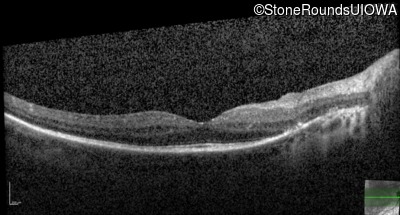

OCT Stack

20/32 -1